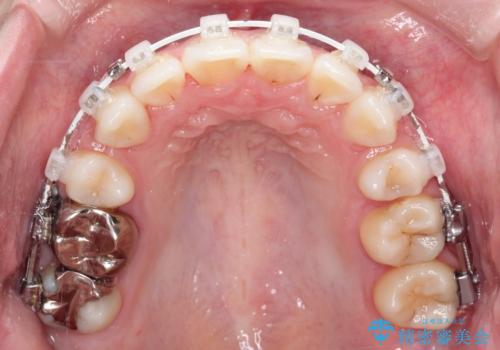

ワイヤー矯正を用いて、欠損部の閉鎖を目的とした後方からの歯の挺出・移動を行いました。

特に、親知らずを活用し、奥歯の噛み合わせを構築することに重点を置きました。